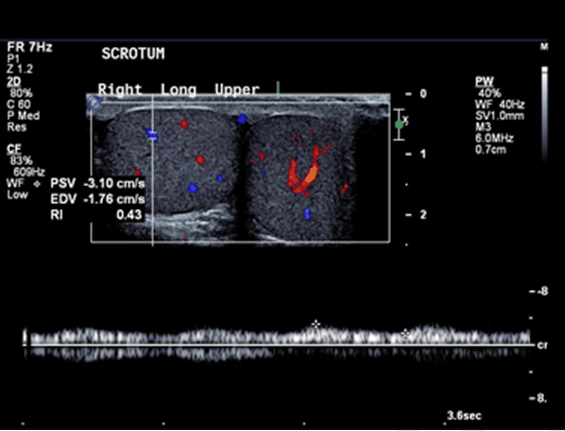

Ultrasound of the scrotum showed polyorchidism with two distinct testes within each hemi-scrotum. The upper left testis measured 3.4x2.5 cm with no Doppler flow to the testis and adjacent hyperemia in the epididymis (Figure 1). The lower left testis measured 1.7x3.3 cm with decreased Doppler flow (Figure 2). The right hemi-scrotum contained two distinct testes measured 2.3x2.6 cm in the right upper testis (Figure 3) and 3.5x3.3 cm in the right lower testis (Figure 4).

Figure 4: Right lower testis with normal Doppler flow and dimensions (3.5x3.3 cm).

The main finding is the presence of a mass with identical echotexture to the ipsilateral testis with the similar flow characteristics to the ipsilateral testis on the color Doppler sonography [5]. In our case, the flow to the left supernumerary testis was absent and the flow to the left ipsilateral testis was also decreased which raised the suspicion of left sided supernumerary testicular torsion.